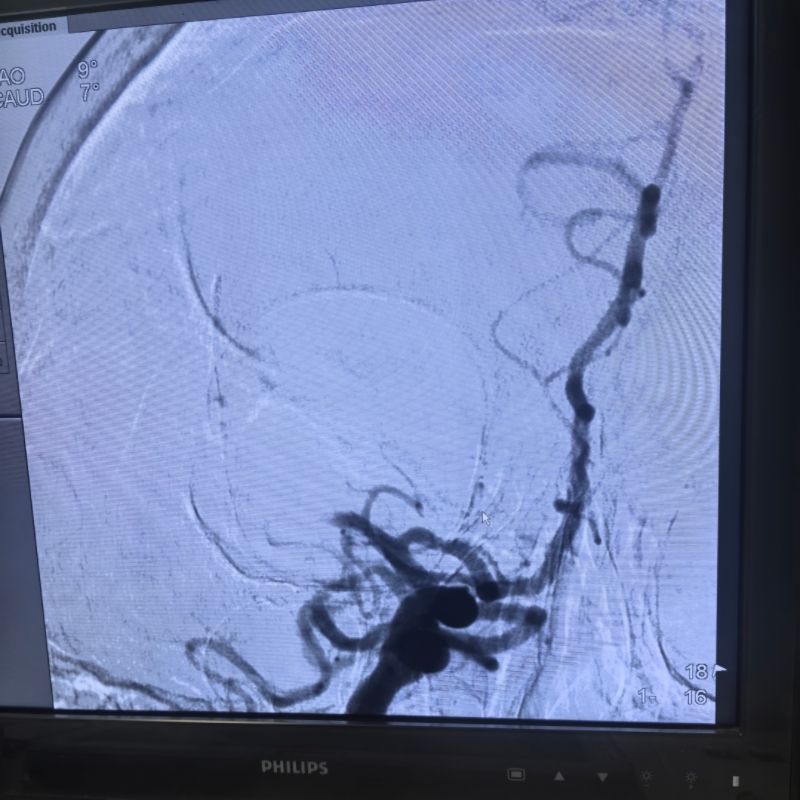

“患者神志不清、肢体瘫痪,核心病因是脑血管闭塞,若不及时取栓,脑细胞会持续坏死,不仅可能终身残疾,还会因病情进展危及生命。躺不平、做不了 CTA 都不是放弃的理由,我们得想办法创造治疗条件!” 神经介入团队傅新民主任、宗海亮主任、陈施吾医生当机立断。他们没有囿于常规检查流程的教条,而是基于指南原则与患者危重症情综合研判:跳过 CTA 直接行数字减影血管造影(DSA),在造影确认大血管闭塞后立即实施取栓,以最直接的方式为抢救争取宝贵时间;同时迅速制定心功能改善方案,在导管室张学萍护士长、朱护师的配合下立即泵入硝酸甘油减轻心脏后负荷,联用利尿剂降低前负荷,双管齐下改善心功能。令人振奋的是,用药后不久,患者的气喘、胸闷症状逐渐缓解,竟然能够平稳平卧 —— 这为取栓治疗打开了关键突破口。

时间就是大脑,每一秒都关乎神经功能的恢复。神经介入团队争分夺秒,快速完成穿刺、造影、取栓一系列操作,全程仅用 1 小时便成功开通闭塞血管。术后,患者顺利转入 ICU 监护,而今天一早,奇迹已然发生:张大妈完全清醒,左侧肢体活动能力明显好转,从生死边缘被成功拉回。